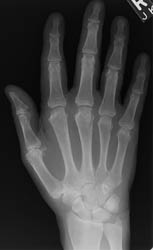

The most commonly affected area of the wrist is at the articulation of the

distal radius and proximal carpal row. There is a strong propensity of CPPD

crystal deposition disease for the 2nd and 3rd metacarpophalangeal joints.

Changes at the interphalangeal joints and other metacarpophalangeal articulations

occur much less frequently and to a much lesser degree

| 2nd-5th MCP | +++ | ![]() ![]() |

| Radiocarpal | +++ | ![]() |